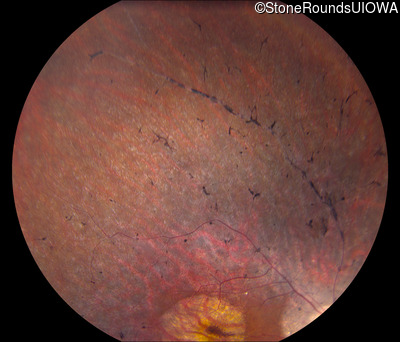

Fundus Photography - Right - 20/50

Exemplar